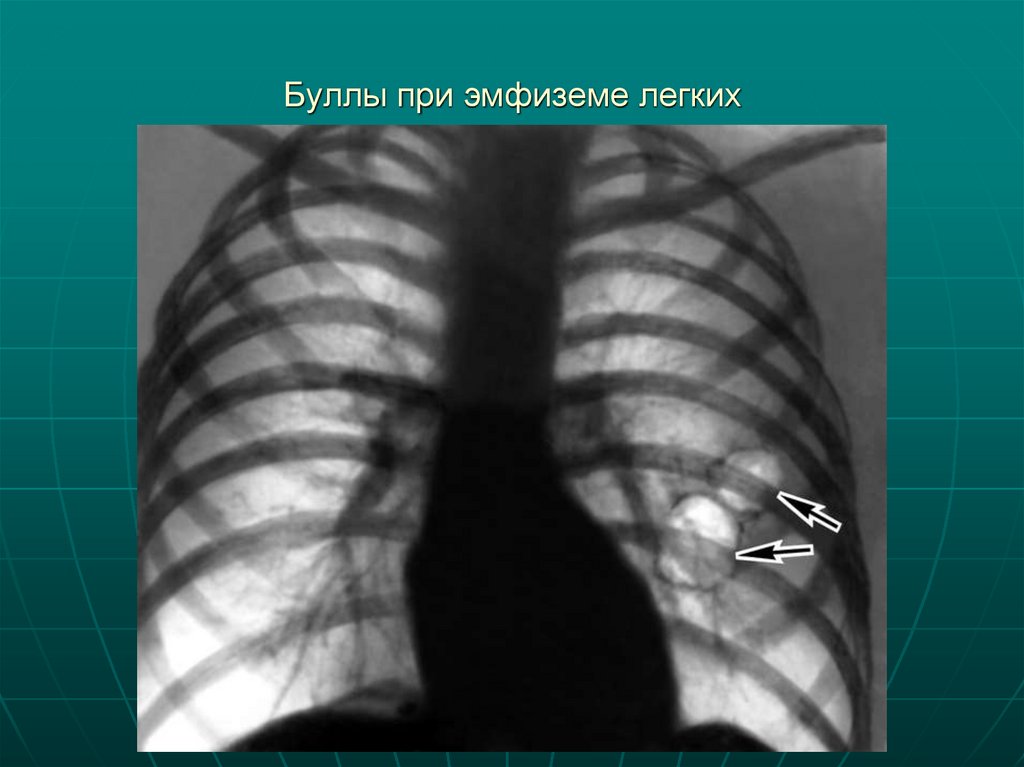

Буллы при эмфиземе легких

19. Буллы при эмфиземе легких